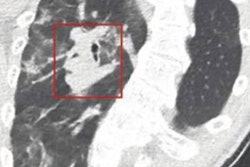

59-year-old man involved in skiing accident. (A) Sagittal reformatted bone window CT image of thoracic spine shows wedge-shaped deformity at T6 and subtle superior endplate deformities at T5 and T8. Arrows denote deformities. (B) Color-coded dual-energy CT shows only T8 deformity is associated with bone marrow edema; T5 and T6 deformities likely represent chronic fractures. Arrows denote deformities. Images and caption courtesy of the American Roentgen Ray Society.Of the 3,159 exams, dual-energy CT was not mentioned in the report in most cases (71.9%). But in those cases that did make use of the technique, dual-energy CT potentially altered clinical management in 9.4%, increased diagnostic confidence in 14.4%, offered relevant new information in 5.6%, and helped characterize incidental findings in 1.4% of cases. Dual-energy CT altered patient management most in the musculoskeletal category, at 89%; of these, 70% of the exams were performed to confirm gout.